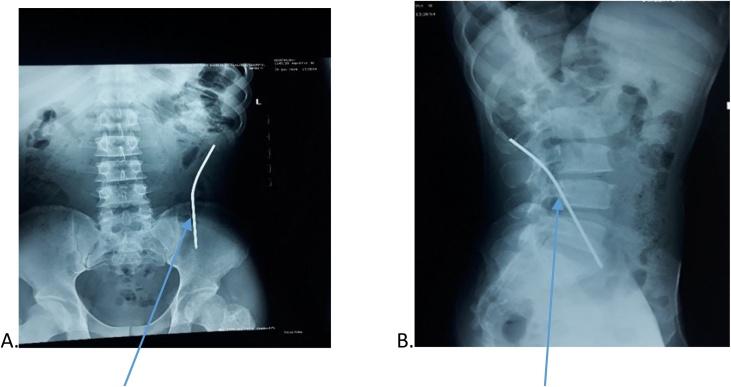

A two-port technique was used to retrieve the pin. These ports consisted of optical supra-umbilical port (10 mm) and left iliac fossa port of 10 mm. They were aligned in the direction of sharp end of the foreign body, to aid retrieval of the Steinmann pin. This procedure was performed on a 34-year-old man who presented with migration of Steinmann pin into abdominal cavity. He had open reduction of old unreduced left posterior hip dislocation. A Steinmann pin with a diameter of 4.5 mm and length of 140 mm was passed through the greater trochanter to the acetabular roof. The protruding end of the pin ought to have been bent. Three weeks post-surgery, the pin migrated. Physical examination revealed vague tenderness over supra pubic region. A hard pointed object was palpable in the right iliac fossa. Abdominal X-ray and ultrasound were suggestive but not definite for pin location.

采用双孔技术取出斯氏针。这两个孔包括脐上光学孔(10毫米)和左髂窝10毫米孔。它们与异物尖锐端的方向对齐,以协助取出斯氏针。该手术在一名34岁男性患者身上进行,该患者的斯氏针迁移至腹腔。他曾接受陈旧性左后髋关节脱位切开复位术。一根直径4.5毫米、长度140毫米的斯氏针穿过大转子至髋臼顶。针的突出端本应弯曲。术后三周,针发生迁移。体格检查发现耻骨上区域有模糊压痛。在右髂窝可触及一个硬的尖状物。腹部X线和超声检查对针的位置有提示作用但不明确。